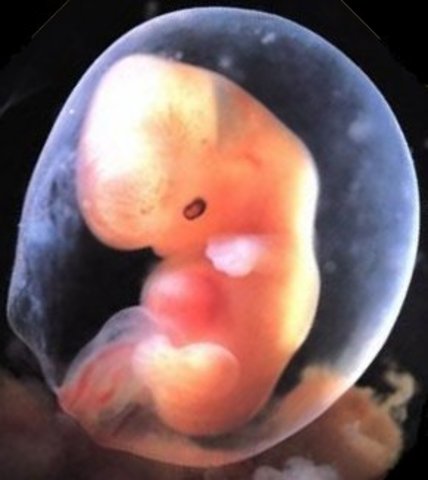

• week 5 Begginning of Embryonic stage

week 5 Begginning of Embryonic stage

cells of the ovum start making the amniotic sac, and placenta. other cells will begin to begin forming the embryo itself. embryo wil double in size by the end of the week. The embryo grows to 5mm

Fact: nerve and spinal chord begin early stages of development.

• week 6 Heartbeat

week 6 Heartbeat

a tube shaped heart and blood vessels begin to form, a heartbeat can be detected from the embryo at this stage.The embryo begins to develop eye pits, the brain beegins development and five part separation, and the cells for what will be the limbs begin their positioning. Embryo has reached the size of 8 mm